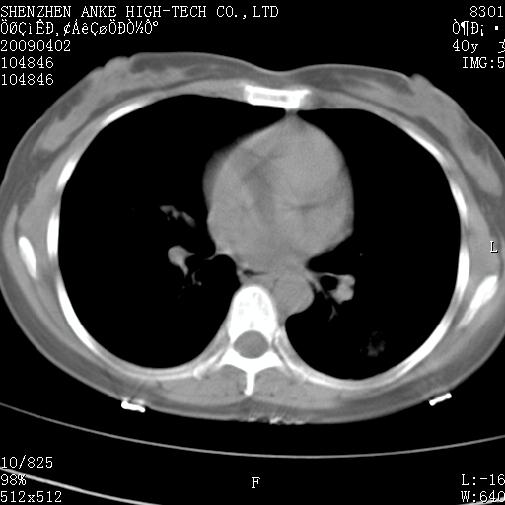

以下是引用随光逐影在2009-4-2 12:16:00的发言:[br]考虑左肺下叶背段继发性肺结核,结核球形成;建议追踪复查。

以下是引用gudu医生在2009-4-2 11:27:00的发言:[br]周围型肺癌

以下是引用卜一在2009-4-2 13:31:00的发言:[br][br] [br] 空洞壁厚不均 胸膜凹陷征。周围型肺癌可能 不排除干酪坏死型肺结核及坏死性肉芽肿。 [br] [br]支持!

以下是引用ct诊断高手在2009-4-2 13:04:00的发言:[br]空洞壁厚不均 胸膜凹陷征。周围型肺癌可能 不排除干酪坏死型肺结核及坏死性肉芽肿。